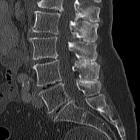

Plain radiograph and CT

- often shows close approximation and contact of adjacent spinous processes (kissing spines)

- resultant enlargement, flattening, and reactive sclerosis of apposing interspinous surfaces